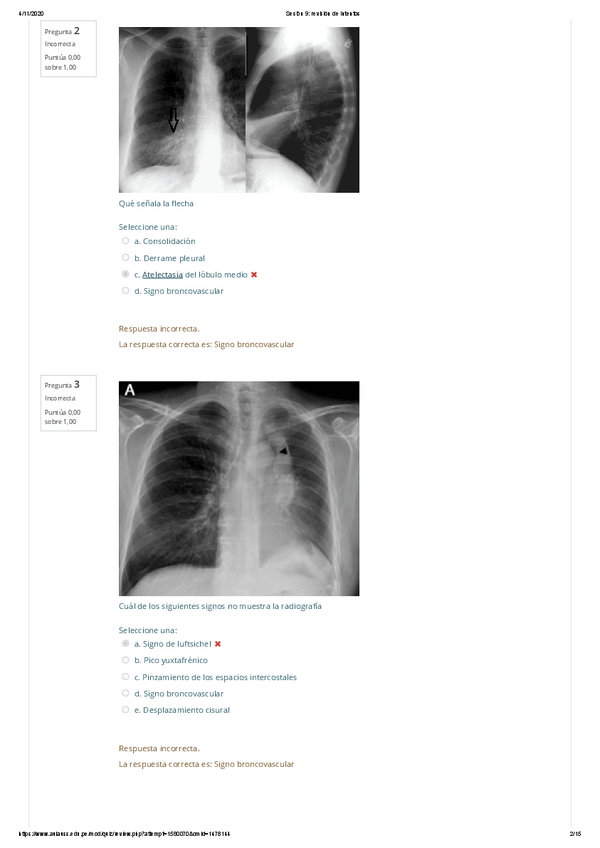

Examen práctico Primer Parcial

18 páginas